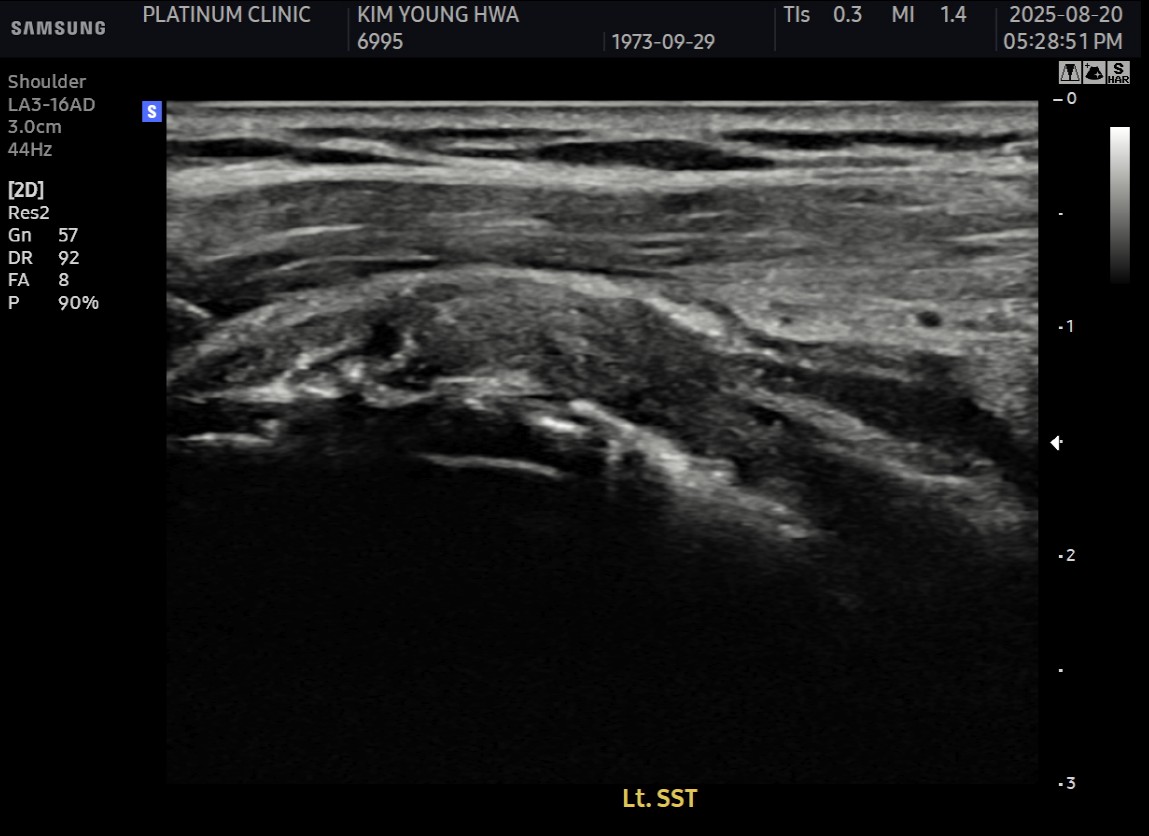

MRI와 초음파 검사 결과:

진단 결과:

- ✓관절면측 부분파열: 약 50%

- ✓점액낭면측 부분파열: 약 35%, 인대 얇아짐 동반

- ✓25년간 반복 사용으로 인한 퇴행성 변화 동반

양쪽 모두 손상된 복합 파열이었습니다.

시술 과정

시술 시간: 약 40분

- ✓관절면측: 봉합 부위 안정적 유지

- ✓점액낭면측: 인대 두께 4.8mm → 6.5mm (1.7mm 증가)